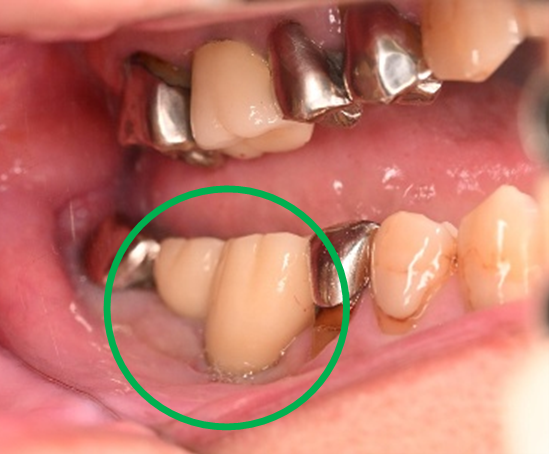

男性 Yさん 60代 (インプラント)

主訴

右下の奥歯の歯肉が痛い。時々血が出たり、腫れたりする。

治療内容

右下のブリッジの支台になっている前方の歯が、歯根破折を起こしていましたので抜歯しました。インプラントを右下第一、第二大臼歯部に2本埋入しました。

所感

実はこの患者さんは、2014年に右下の第二大臼歯(一番奥の歯から2番目の歯)を歯根破折により抜歯し、その際の治療法としてブリッジを選択されました。そして今回、ブリッジを支えていた歯(第一大臼歯)がついに歯根破折を起こしてしまいました。

ブリッジは、3本分の歯を2本の歯で支えるため、支える歯の負担が大きくなり、歯根破折を起こす危険性が高くなります。

今回の抜歯後は、歯が2本ない状態になるので、そこを補う方法についてご説明しました。選択肢は再度ブリッジを入れるか、インプラントになります。ブリッジにして支える歯がまた折れてしまうと歯が3本ない状態になる可能性があるため、インプラントを選択されました。もし11年前にブリッジではなくインプラントを選んでおられたら、今回の歯根破折や抜歯は起きなかったかもしれません。ブリッジは、噛む力の強い方、歯ぎしりをする方、硬い食べ物が好きな方は、支えの歯の負担がより大きくなるのでおすすめできません。

インプラントは、それ自身が単独で植立しているので、他の歯に負担がかかりません。インプラントは、欠損を補う最良の方法と考えます。

インプラント2本:¥726,000(税込)

Before

抜いた歯 真二つにわれています

After